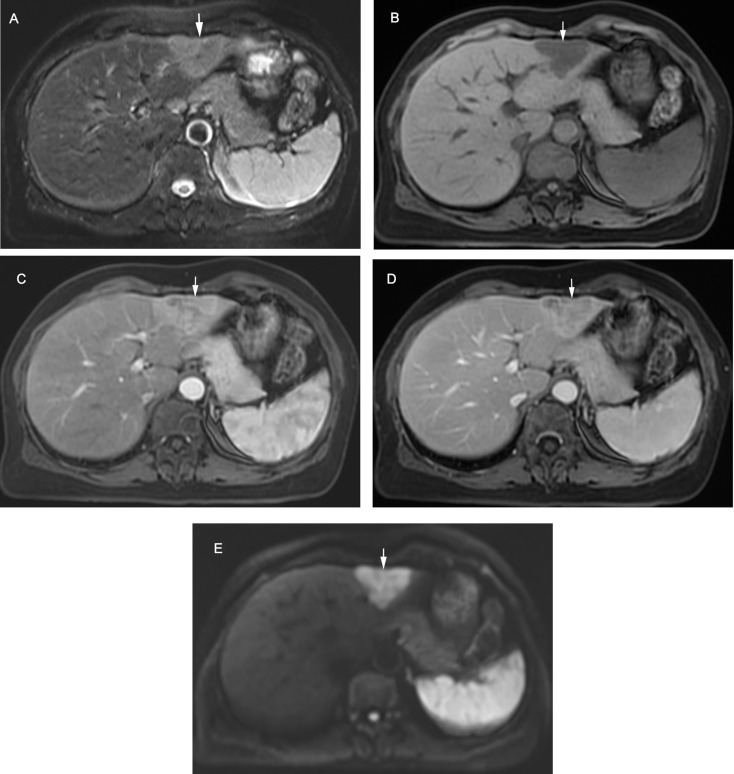

{"title":"Assessment of intrahepatic cholangiocarcinoma with LI-RADS in the high-risk population: MRI diagnosis and postoperative survival.","authors":"Ruofan Sheng, Beixuan Zheng, Yunfei Zhang, Chun Yang, Dong Wu, Jianjun Zhou, Mengsu Zeng","doi":"10.1186/s40644-025-00860-6","DOIUrl":null,"url":null,"abstract":"<p><strong>Background: </strong>The precise impact of LI-RADS-defined risk factors on the diagnosis and prognosis of intrahepatic cholangiocarcinoma (iCCA) remains unclear.</p><p><strong>Objective: </strong>To assess the value of LI-RADS categories and features for iCCA diagnosis, focusing on the diagnostic and prognostic implications of LI-RADS-defined risk factors.</p><p><strong>Methods: </strong>Totally 214 high risk patients, including 107 surgically-confirmed solitary iCCAs and 107 hepatocellular carcinomas (HCC) from two centers were retrospectively enrolled. Clinical and MRI features based on LI-RADS v2018 were compared, and the performance of targetoid features for discriminating iCCA was evaluated. Recurrence-free survival (RFS) was compared across different pathologic diagnoses and LI-RADS categories. Multivariate Cox analysis was performed to identify the independent risk factors for RFS.</p><p><strong>Results: </strong>In the LI-RADS defined high-risk patients, iCCAs differed from HCCs in MRI manifestation. The LR-M category enabled the accurate classification of most iCCAs (89/107, 83.2%), achieving high sensitivity (83.2%), specificity (85.1%), and accuracy (84.1%). The optimal diagnostic performance for iCCA was achieved when at least one targetoid appearance was required for LR-M categorization (AUC = 0.828). Although 26.2% iCCAs presented at least one major feature and 15.0% iCCAs were miscategorized as probably or definitely HCC, only one iCCA case was categorized as LR-5. RFS varied according to both pathologic diagnosis (P = 0.030) and LI-RADS category (P = 0.028), with LI-RADS category demonstrating an independent association with RFS (HR = 1.736, P = 0.033).</p><p><strong>Conclusions: </strong>In high-risk patients, iCCAs frequently exhibit HCC major features, leading to miscategorization as probable HCC. However, the LR-5 category remains highly specific for ruling out iCCA. Furthermore, in high-risk patients with solitary resected iCCA or HCC, LI-RADS category enables the prediction of postsurgical prognosis independently from pathological diagnosis.</p>","PeriodicalId":9548,"journal":{"name":"Cancer Imaging","volume":"25 1","pages":"40"},"PeriodicalIF":3.5000,"publicationDate":"2025-03-26","publicationTypes":"Journal Article","fieldsOfStudy":null,"isOpenAccess":false,"openAccessPdf":"https://www.ncbi.nlm.nih.gov/pmc/articles/PMC11938583/pdf/","citationCount":"0","resultStr":null,"platform":"Semanticscholar","paperid":null,"PeriodicalName":"Cancer Imaging","FirstCategoryId":"3","ListUrlMain":"https://doi.org/10.1186/s40644-025-00860-6","RegionNum":2,"RegionCategory":"医学","ArticlePicture":[],"TitleCN":null,"AbstractTextCN":null,"PMCID":null,"EPubDate":"","PubModel":"","JCR":"Q2","JCRName":"ONCOLOGY","Score":null,"Total":0}

Results: In the LI-RADS defined high-risk patients, iCCAs differed from HCCs in MRI manifestation. The LR-M category enabled the accurate classification of most iCCAs (89/107, 83.2%), achieving high sensitivity (83.2%), specificity (85.1%), and accuracy (84.1%). The optimal diagnostic performance for iCCA was achieved when at least one targetoid appearance was required for LR-M categorization (AUC = 0.828). Although 26.2% iCCAs presented at least one major feature and 15.0% iCCAs were miscategorized as probably or definitely HCC, only one iCCA case was categorized as LR-5. RFS varied according to both pathologic diagnosis (P = 0.030) and LI-RADS category (P = 0.028), with LI-RADS category demonstrating an independent association with RFS (HR = 1.736, P = 0.033).

Conclusions: In high-risk patients, iCCAs frequently exhibit HCC major features, leading to miscategorization as probable HCC. However, the LR-5 category remains highly specific for ruling out iCCA. Furthermore, in high-risk patients with solitary resected iCCA or HCC, LI-RADS category enables the prediction of postsurgical prognosis independently from pathological diagnosis.